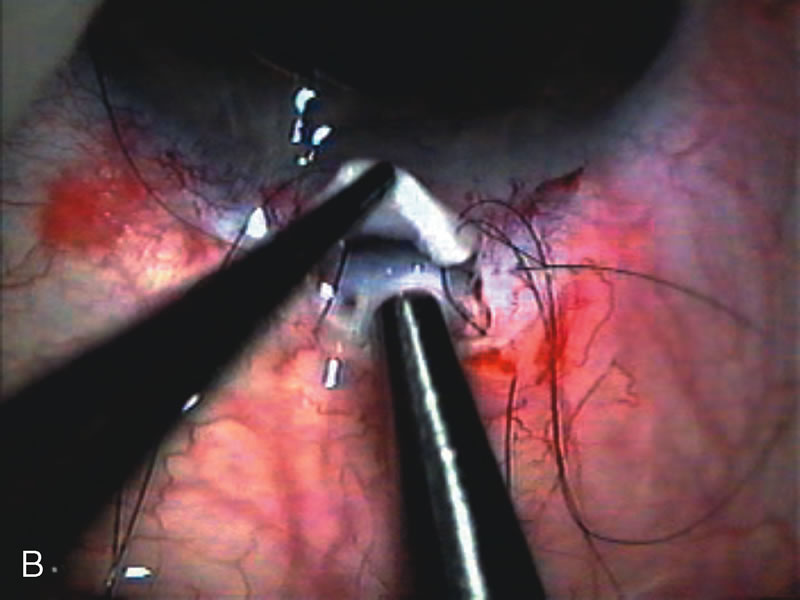

Fig. 7. Phacotrabeculectomy adjacent to a failed filter in cataractous eye. The ability to combine small-incision cataract extraction with trabeculectomy all through the same incision adjacent to the failed filter allows the surgeon to work in a familiar superior area. Avoiding incisions into the existing bleb decreases conjunctival buttonholes, hypotony, operating room time, and subconjunctival bleeding. A. Appearance of failed bleb with exposure of superior temporal quadrant gained with a corneal traction suture. B. Prepare a limbus-based conjunctival flap and a scleral flap. C. This bleb is at high risk to fail again justifying the need for MMC, 0.2 mg/cc applied on a pledget for 4 minutes. D. Insert the keratome and perform phacotrabeculectomy in the usual fashion.